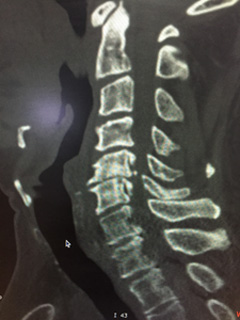

Cervical Myelopathy OPLL